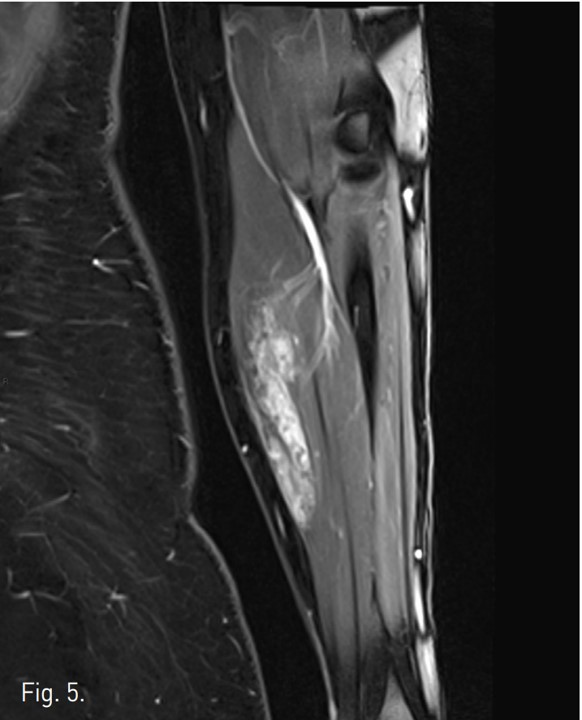

Venography demonstrates dilated, tortuous veins along the medial aspect of the proximal forearm draining into normal veins (Fig. 1). Negative digital subtraction angiography shows filling-defects from displaced contrast material in the vascular malformation during sodium tetradecyl sulfate foam injection (Fig. 2). A native image of the forearm demonstrates stasis of contrast material within the venous malformation after foam sclerotherapy (Fig. 3). T2 STIR imaging shows a 10.3 x 2.5 x 2.3 cm high signal intensity mass centered within the flexor digitorum superficialis consistent with slow-flow vascular malformation. The high signal represents the extent of the vascular malformation as well as post-treatment edema or inflammation (Fig. 4). Post-contra st T1 imaging with fat suppression demonstrates heterogeneous enhancement of the mass with notable areas of low signal representing the areas of thrombosis/sclerosis. The residual irregular enhancement represents postprocedural inflammation. Of note, there are no enhancing serpiginous structures (Fig. 5).

Fig. 5.

Fig. 5. Post-contrast T1 imaging with fat suppression demonstrates heterogeneous enhancement of the mass wi th notable areas of low signal representing the areas of thrombosis/sclerosis. The residual irregular enhancement represents post-procedural inflammation. Of note, there are no enhancing serpiginous structures.